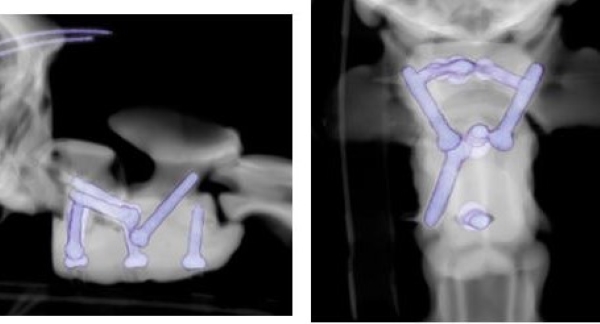

3Dプリント特殊ねじのX線写真(本人のフェイスブックから)